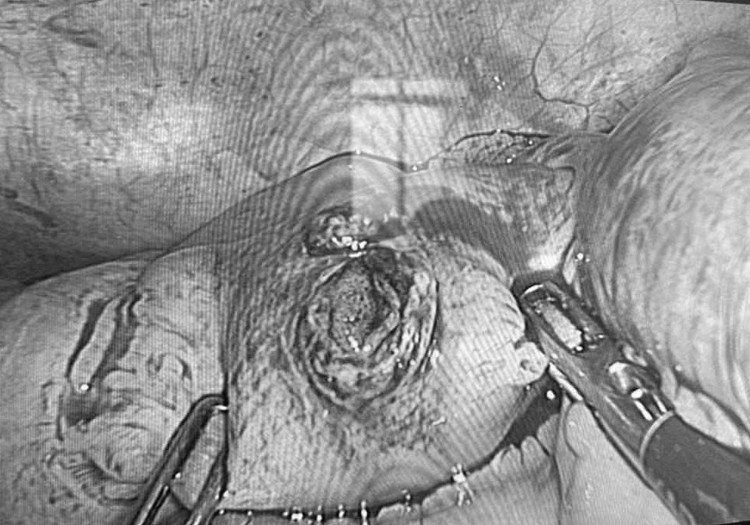

Vết thủng ở ruột non người bệnh - Ảnh BVCC

Ngay khi tiếp nhận, các bác sĩ tiến hành thăm khám lâm sàng và chụp cắt lớp vi tính ổ bụng. Kết quả cho thấy dị vật là một chiếc đinh xuyên qua thành bụng trái và găm trực tiếp vào ruột non, tiềm ẩn nguy cơ nhiễm trùng ổ bụng và biến chứng nặng nếu không xử trí kịp thời.

Trước tình trạng nguy cấp, các bác sĩ Khoa Ngoại Tổng hợp đã nhanh chóng chỉ định phẫu thuật nội soi cấp cứu. Ê-kíp phẫu thuật tiến hành lấy dị vật, khâu lỗ thủng ruột non, đồng thời khâu phục hồi thành bụng.